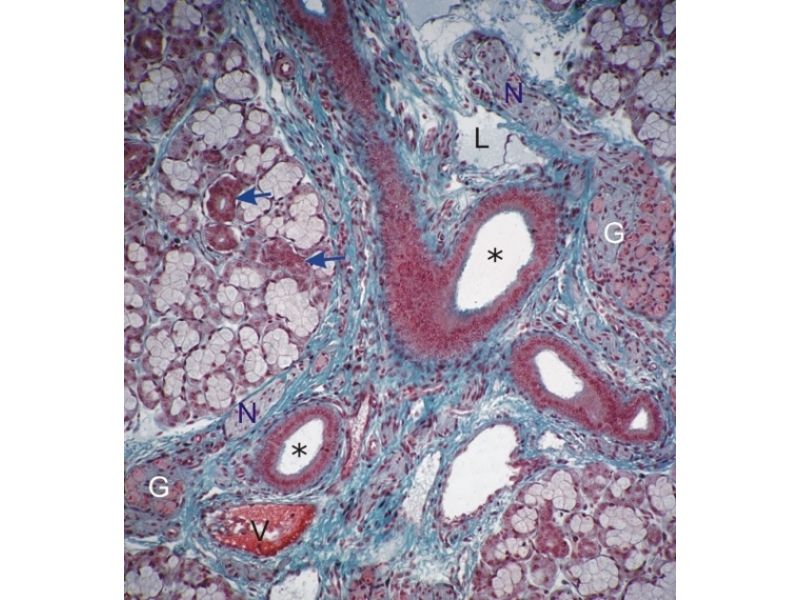

Mammary Gland and Nipple

Mammary gland - slide 57

Nipple - slide 15